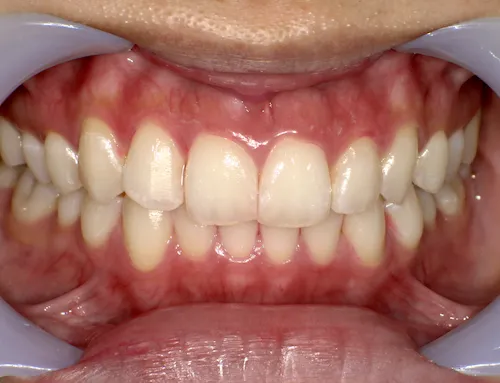

痛くない・しみないのに、45分で白くなる。

45分で白くなる。